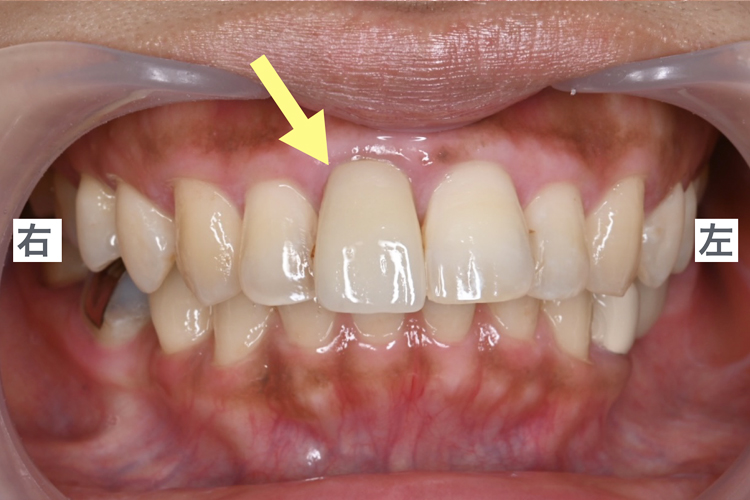

初診時の口腔内写真

前歯の形をきれいにしたい。数年前に入れた被せ物の形が変ということでご来院。

特に、歯の色が周りと合っていない、隣の前歯と大きさが合っていないことが気になるとのことでした。

所見

- 右上1番の補綴物(被せ物)が、

他の歯に比べて長い - 補綴物の色味が単一で自然な色調ではない

(全体と馴染んでいない) - 右上の前歯が出ているように見える、

大きく見える印象 - 補綴物周りの歯肉のラインがいびつ、

歯肉全体に色素沈着が認められる